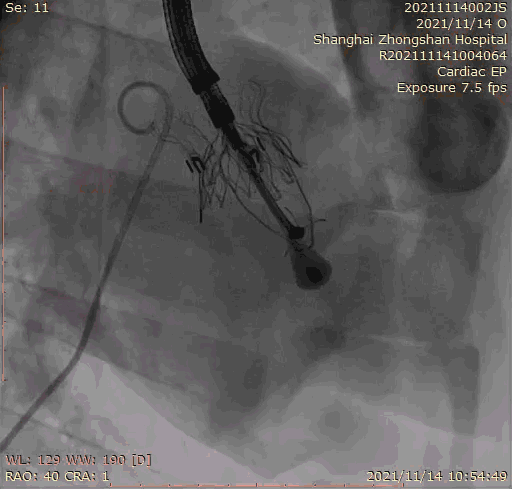

本次臨床前研究經(jīng)右側(cè)頸靜脈置入LuX-Valve Plus輸送系統(tǒng)可調(diào)彎鞘管,在DSA及超聲引導(dǎo)下將人工三尖瓣瓣膜植入到原有三尖瓣位置,利用獨(dú)特的錨定技術(shù)將人工瓣膜支架可靠固定在預(yù)定的位置。

上海中山醫(yī)院葛均波院士、錢菊英院長、周達(dá)新教授、潘文志教授、潘翠珍教授、李偉教授共同完成此次臨床前研究。術(shù)后葛均波院士對(duì)Lux-Valve Plus的器械操作性能給予了高度評(píng)價(jià),DSA和超聲影像也顯示出在本次研究中Lux-Valve Plus的安全性和有效性俱佳。